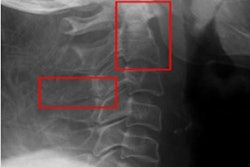

Detection of pediatric c-spine injuries and the process by which cervical collars are removed is of the utmost importance, as missed injuries can be devastating, the authors explained. C-spine x-ray has been shown to be a valid screening tool for c-spine injury when coupled with a normal physical examination, and it is recommended by the Pediatric Trauma Society, they added.

Thus, the group conducted a retrospective review of cases at their level 1 pediatric trauma center from 2012 to 2021. The hospital’s protocol is to start with x-ray in patients with Glasgow Coma Scale (GCS) scores between 14 and 15 and then go to multidetector CT in patients with a depressed GCS score. The researchers compared a group with negative c-spine x-ray and no additional imaging to a group with negative c-spine x-ray followed by additional c-spine CT and/or MRI.